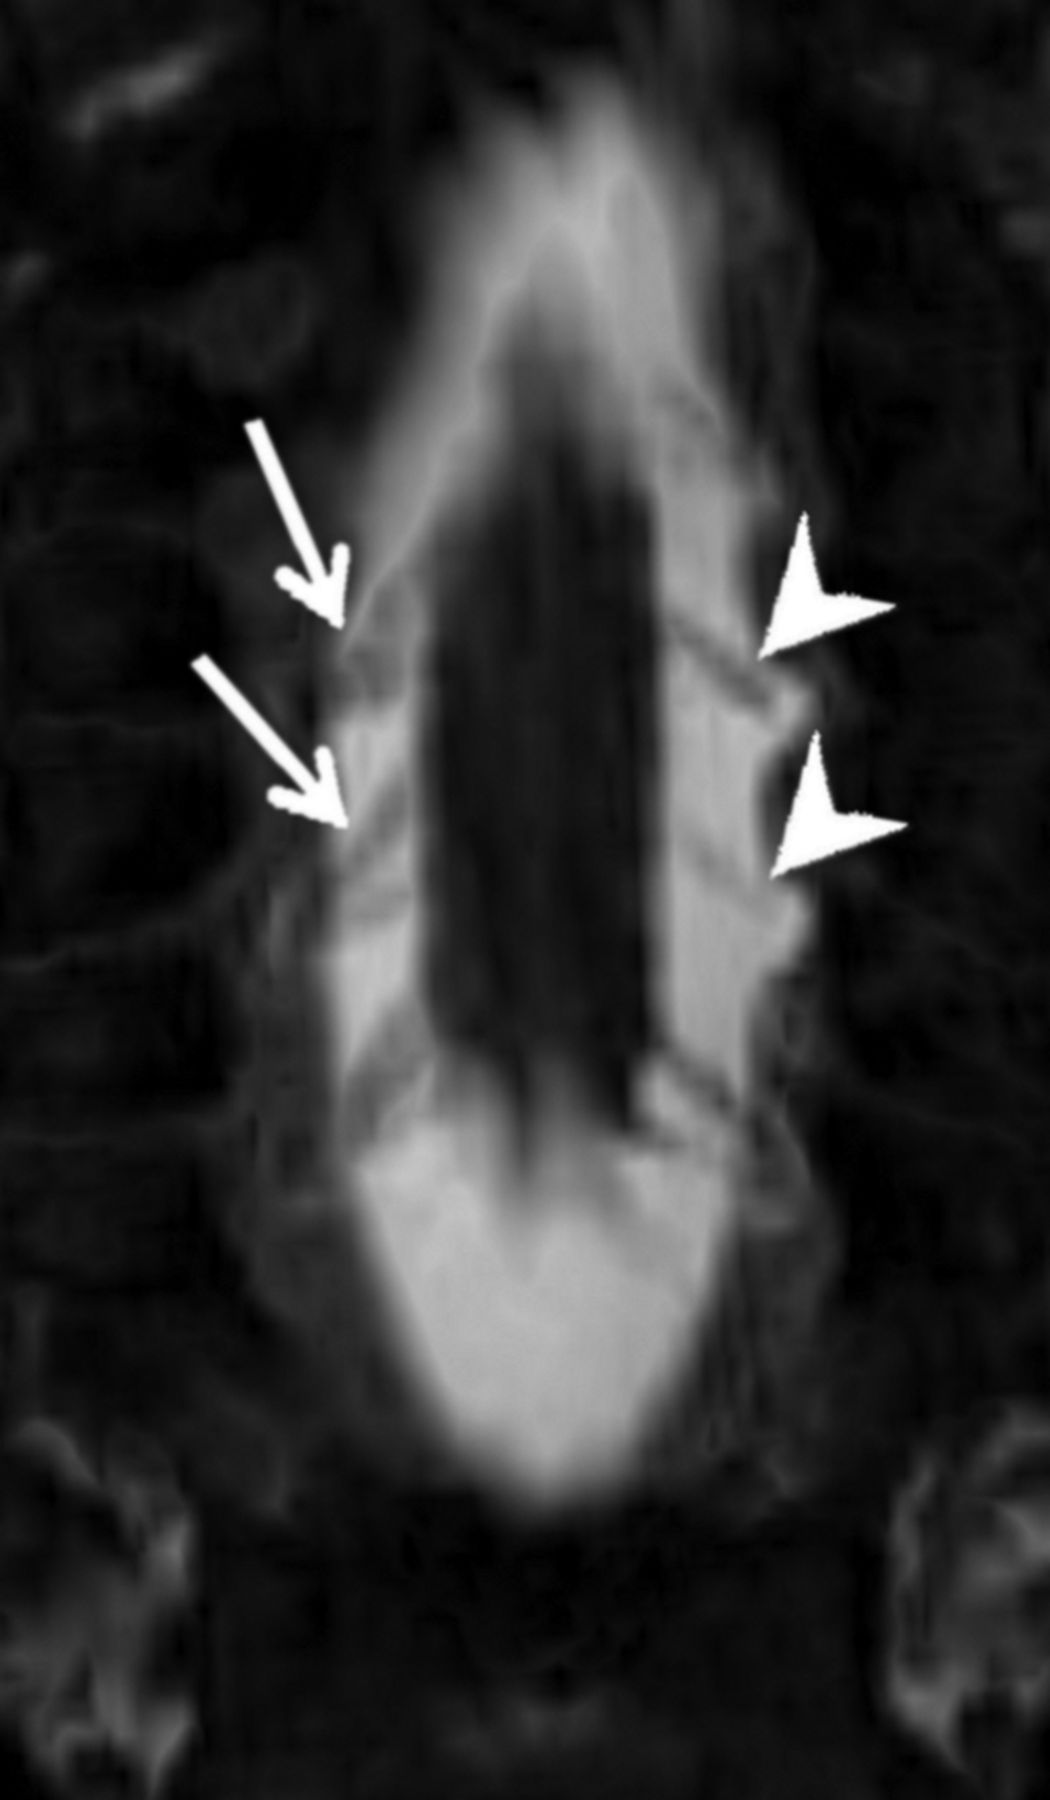

Coronal minimum-intensity-projection image from an MR myelogram demonstrating thinned left-sided ventral rootlets at C6 and C7 (arrowheads), relative to the normal fan-shaped right-sided ventral rootlets on the contralateral side at the same levels (arrows). Base resolution was 0.6-mm isotropic, with a 2-mm minimum-intensity-projection slab.